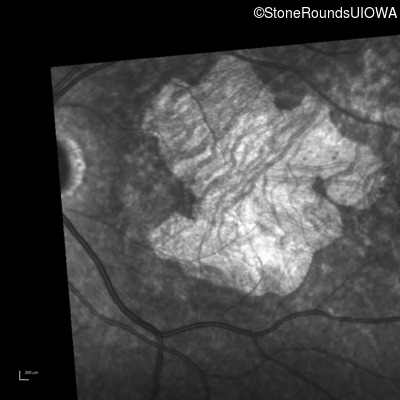

Infrared Fundus Photograph - Right - 20/40

Exemplar